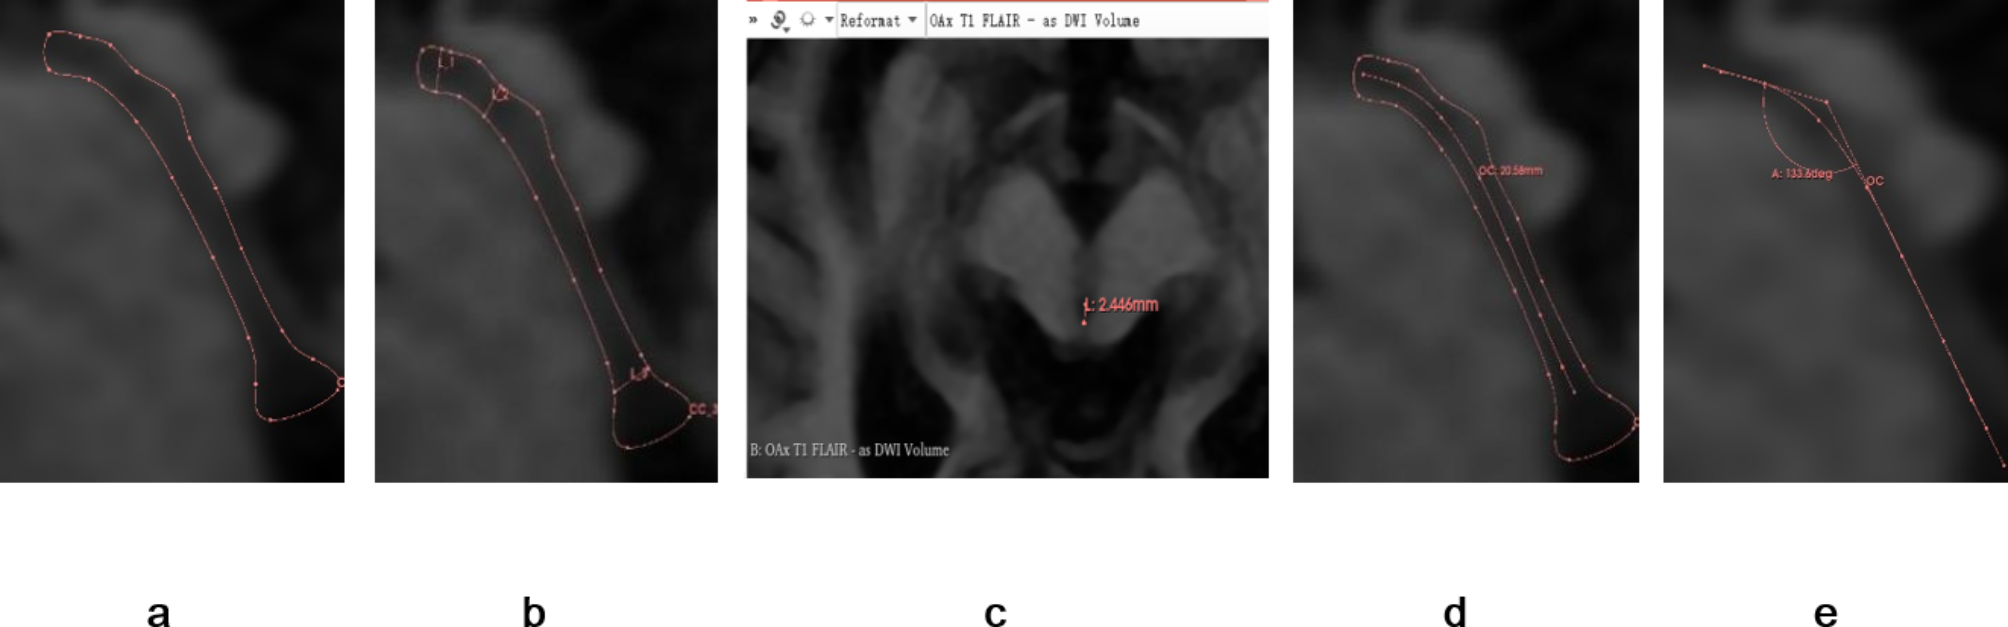

Fig. 1

Analysis of mesencephalic aqueduct morphology on magnetic resonance images of the brainstem. (a) Borders of the mesencephalic aqueduct in the mid-sagittal plane. (b) Diameters of the mesencephalic aqueduct at the rostral opening with the third ventricle, constriction, and termination at the fourth ventricle. (c) Measurement of these same aqueduct diameters in the axial plane using the automatic linkage feature of 3D Slicer. (d) Length of the mesencephalic aqueduct. (e) Angle between the anterior upper and posterior lower segments of the mesencephalic aqueduct. Segments are separated by the constriction (as shown in b).